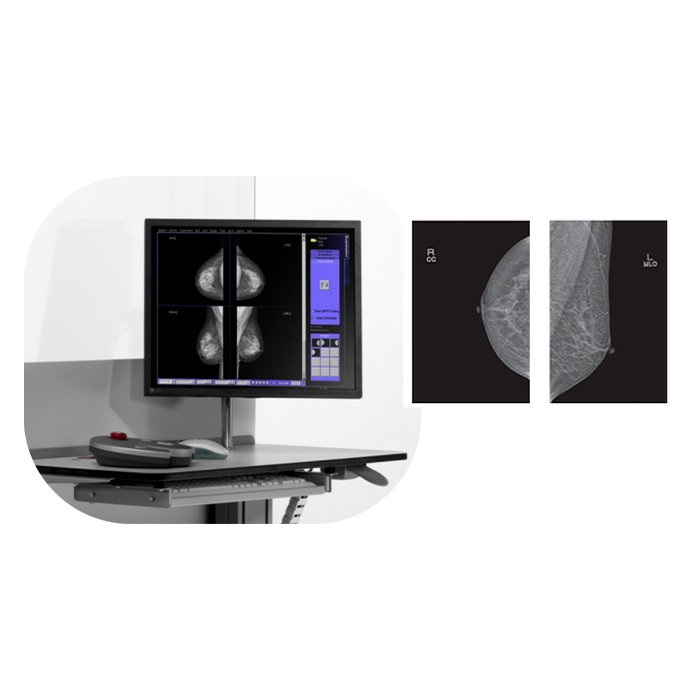

Маммограф PINKVIEW-AT DR Plus Expert Bemems

Маммограф PINKVIEW-AT DR Plus Expert Bemems: Цифровая точность для ранней диагностики

Цифровой маммограф PINKVIEW-AT DR Plus Expert от компании Bemems представляет собой современное диагностическое решение, созданное для проведения высокоточных скрининговых и диагностических исследований молочных желез. Это оборудование сочетает в себе передовые цифровые технологии, эргономичный дизайн и ориентированность на комфорт пациентки, что делает его надежным выбором для оснащения медицинских учреждений.

Ключевым преимуществом системы является прямая цифровая технология (DR) с плоскопанельным детектором, которая обеспечивает получение изображений исключительного качества при минимальной дозовой нагрузке. Это позволяет врачу-рентгенологу выявлять минимальные изменения в тканях на ранних стадиях, что критически важно для успешного лечения.

- Оптимизация рабочего процесса: Мгновенное получение изображения на монитор врача, интеграция с системой архивации и передачи изображений (PACS) и удобное программное обеспечение ускоряют обследование и повышают пропускную способность кабинета.

| Режимы съемки | Стандартные проекции (CC, MLO), при необходимости – дополнительные (например, увеличенная) |

| Программное обеспечение | Специализированное ПО для визуализации, обработки изображений, интеграции с PACS/HIS |